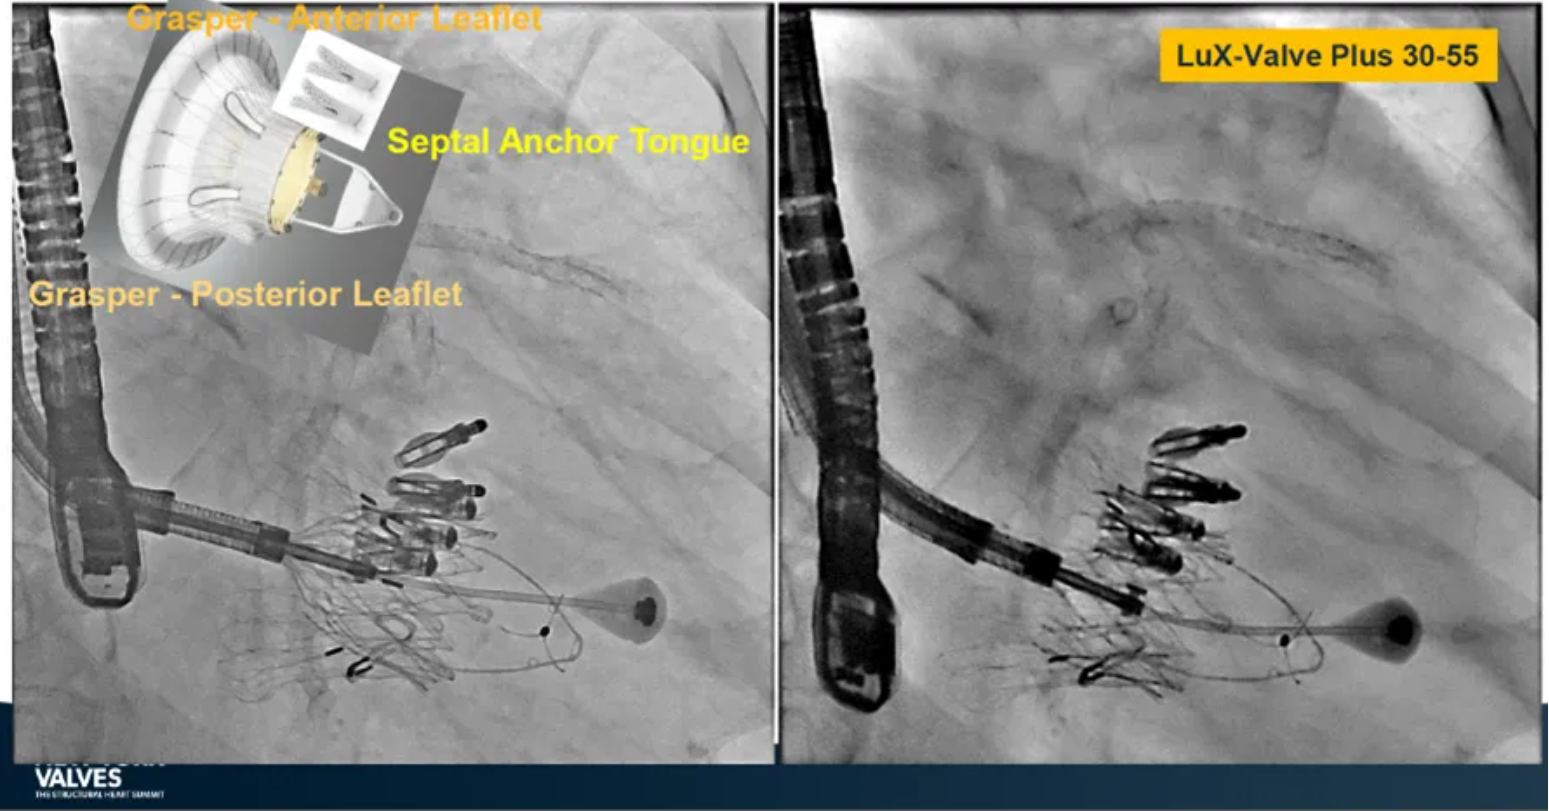

LuX-Valve Plus是健世科技(Jenscare,9877.HK)推出的全新一代經(jīng)頸靜脈三尖瓣置換系統(tǒng)(Transjugular Tricuspid Valve Replacement System),其創(chuàng)新性地采用頸靜脈作為手術(shù)入路,在不依賴徑向支撐力的情況下借助室間隔錨定、瓣葉夾持技術(shù)構(gòu)成其多重錨定結(jié)構(gòu),并通過自適應編織環(huán)有效進行心房側(cè)封堵,呈現(xiàn)更好的安全性和有效性。